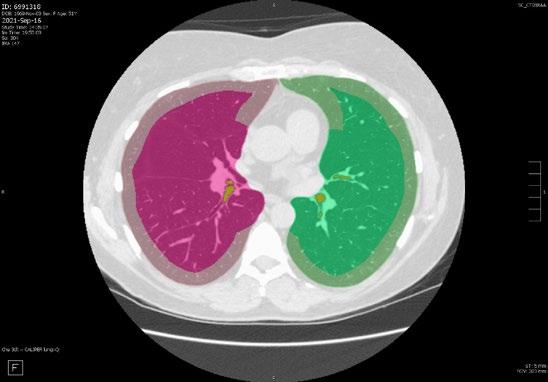

Radiogenomics Relationship of Nonsmall Cell Lung Cancer: Preliminary Results

Keywords: Cancer, lung, radiogenomics, radiology.

BACKGROUND AND AIMS

Radiomics, an emerging paradigm in medical imaging, entails the quantitative analysis of tumour features, and has exhibited potential in predicting treatment responses and outcomes. Furthermore, within the domain of -omics assessments, the significance of comprehensive genetic evaluation in non-small cell lung cancer (NSCLC) is on the rise, influenced by both biological and therapeutic considerations.

The aim of this study was to correlate radiomics features with the genetic results obtained from liquid biopsy in patients with lung tumours. The prediction of tumour genetics in radiomics relies on the presumption of conducting a non-invasive evaluation of molecular characteristics in tumour tissues, which can be challenging in certain tumour types, such as NSCLC. Therefore, in this context, the authors considered it pertinent to explore and generate hypotheses regarding the technical feasibility of identifying associations between genomics acquired through liquid biopsy assessments and radiomics.

MATERIALS AND METHODS

This observational, prospective study integrated radiomic perspectives using CT and genomic perspectives, through next-generation sequencing applied to liquid biopsies.

The authors included 62 patients with NSCLC who underwent pre-surgery CT (Revolution™ 128 MDCT, GE HealthCare, Chicago, Illinois, USA) at the Radiology Department of Campania University Luigi Vanvitelli, Naples, Italy. Every patient for whom liquid biopsy was performed gave informed consent for the genetic analysis. For the radiomic analysis, image processing CT volumes were manually delineated using ITK-SNAP 3.8.0 (University of Pennsylvania, Philadelphia, USA). Radiomics features (first order: Gray Level Co-occurrence Matrix, Gray Level Run Length Matrix, Gray Level Size Zone, Gray Level Dependence Matrix, and Neighbouring Gray Tone Difference Matrix) were computed using Pyradiomics1 in Python 3.7 (Python Software Foundation, USA) environment.

Radiomic features were derived from CT images, and genetic assessments were performed using a comprehensive panel targeting 523 cancerrelated genes. For the statistical analysis, association between radiomic features and gene mutations were assessed using feature importance based on receiver operating characteristic curve analysis; moreover, a machine learning approach based on support vector machine was used to evaluate the ability of radiomic features to predict gene mutations.

Associations between radiomic features and genetic mutations were established using the area under the receiver operating characteristic curve. Machine learning techniques, including support vector machine classification, aimed to predict genetic mutations based on radiomic features. The prognostic impact of selected gene variants was assessed using Kaplan–Meier curves and log-rank tests.

RESULTS

Sixty-two patients underwent screening, with 53 being comprehensively characterised radiomically and genomically. This group was predominantly male (68.4%), and adenocarcinoma was the prevalent histological type (73.7%). Most patients exhibited ECOG Performance Status of 0 or 1 (87.7%), and 91.2% had a history of former or current smoking. Disease staging was distributed across I–II (38.6%), III (31.6%), and IV (29.8%). Significant correlations were identified with mutations

Abstract ● ECR 2024 24 Radiology ● April 2024 ● Creative Commons Attribution-Non Commercial 4.0

of ROS1 p.Thr145Pro (shape_Sphericity), ROS1 p.Arg167Gln (glszm_ZoneEntropy, firstorder_TotalEnergy), ROS1 p.Asp2213Asn (glszm_GrayLevelVariance, firstorder_ RootMeanSquared), and ALK p.Asp1529Glu (glcm_Imc1). Patients with the ROS1 p.Thr145Pro variant demonstrated markedly shorter median survival compared to the wild-type group (9.7 months versus not reached; p=0.0143; hazard ratio: 5.35; 95% confidence interval: 1.39–20.48).

CONCLUSION

This study contributes to advancing the prediction of cancer genetics through the application of non-invasive radiomic techniques. The prediction of tumour genetics in radiomics hinges on the assumption of conducting a non-invasive assessment of molecular characteristics in tumour tissues, which can pose challenges in certain tumour types, such as NSCLC. Therefore, within this context, the authors deemed it relevant to explore and formulate hypotheses regarding the technical feasibility of identifying associations between genomics obtained through liquid biopsy assessments and radiomics.

Specific radiomic features illustrate the capability to predict non-synonymous mutations of ROS1 and ALK in patients with NSCLC. Investigating the prediction of cancer genetics using non-invasive radiomic techniques represents an innovative frontier in scientific research, which is currently undergoing extensive investigation. Research on the use of conventional CT features and CT image-based radiomic features to predict the gene mutation status of lung cancer is still in its nascent stages.

The integration of radiomic techniques in predicting cancer genetics holds potential, but is constrained by cost and technological limitations. Despite these challenges, the authors’ study explores the relationships between genomics and radiomics, revealing specific genetic variants associated with radiomic features. While acknowledging limitations, particularly the small sample size and the lack of actionable mutations, this research lays the groundwork for broader investigations aiming to link radiomics and genomics in NSCLC. The ultimate objective is to improve prognostic accuracy and refine therapeutic strategies. ●